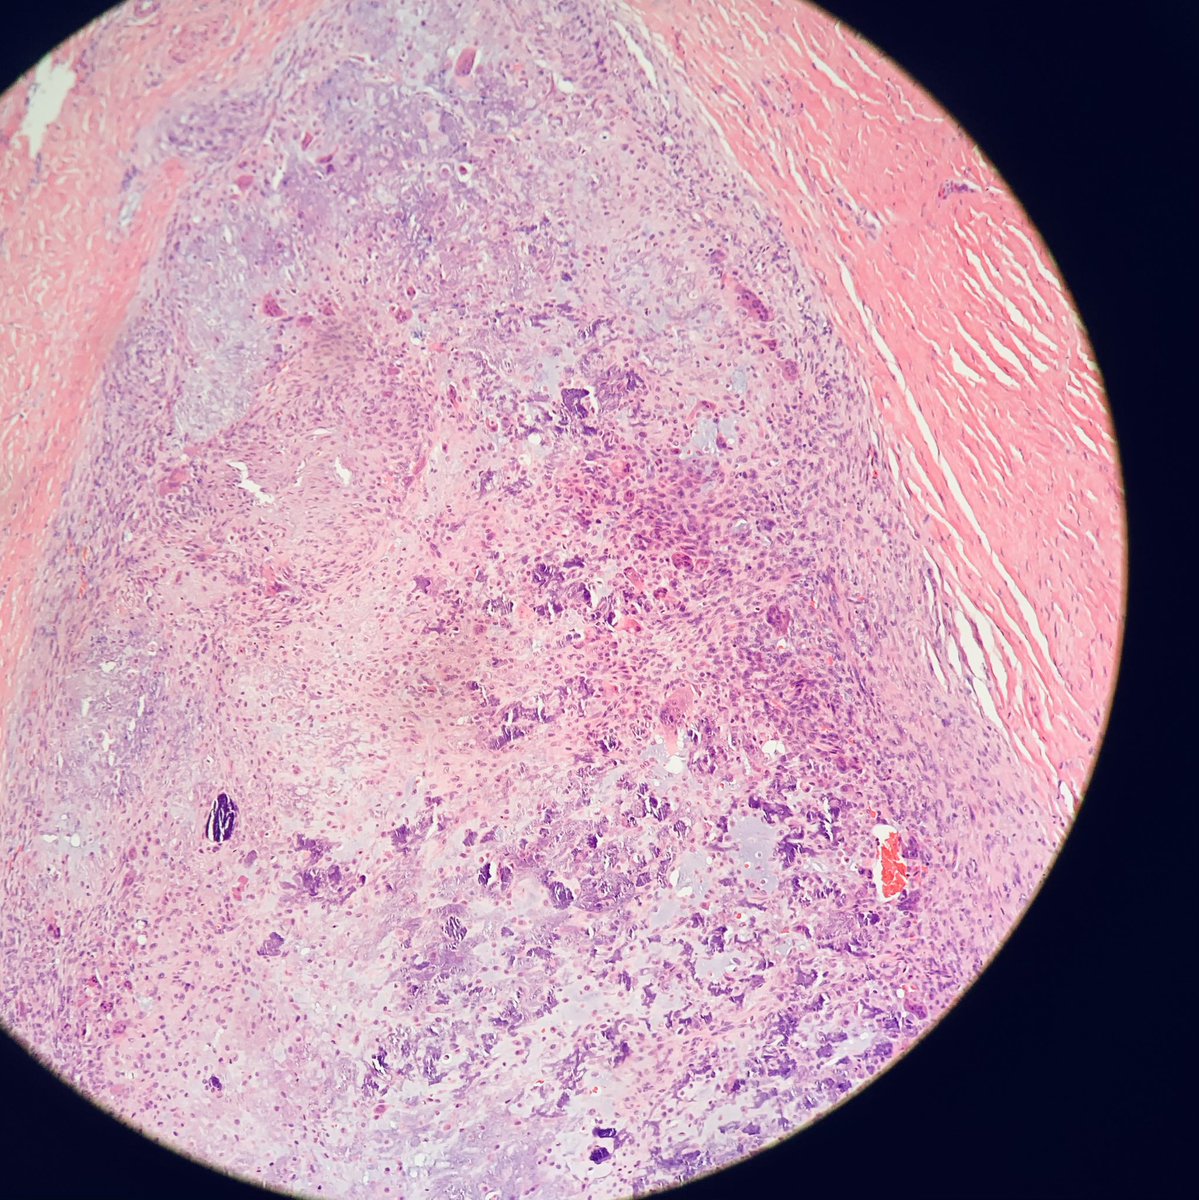

#bstpath I know it is Friday. But I do have this case for your opinion . It is an index finger amputation with a 2.5 cm mass. There are quite some giant cells. I intend to call it giant cell tumor of tendon sheath, but the prominent chondroid changes are the first time for me.1/